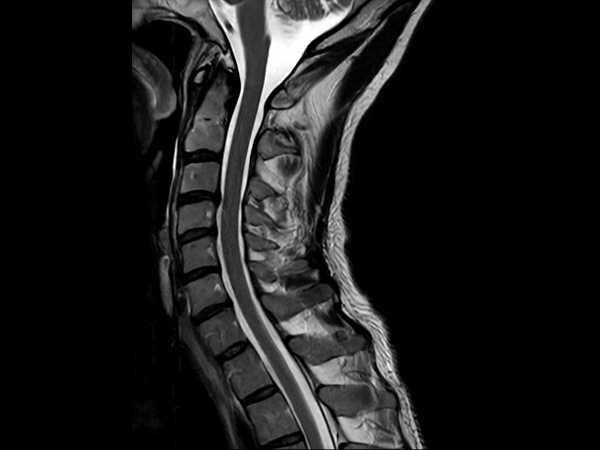

High quality Cervical Spine imaging with SmartSpeed Precise